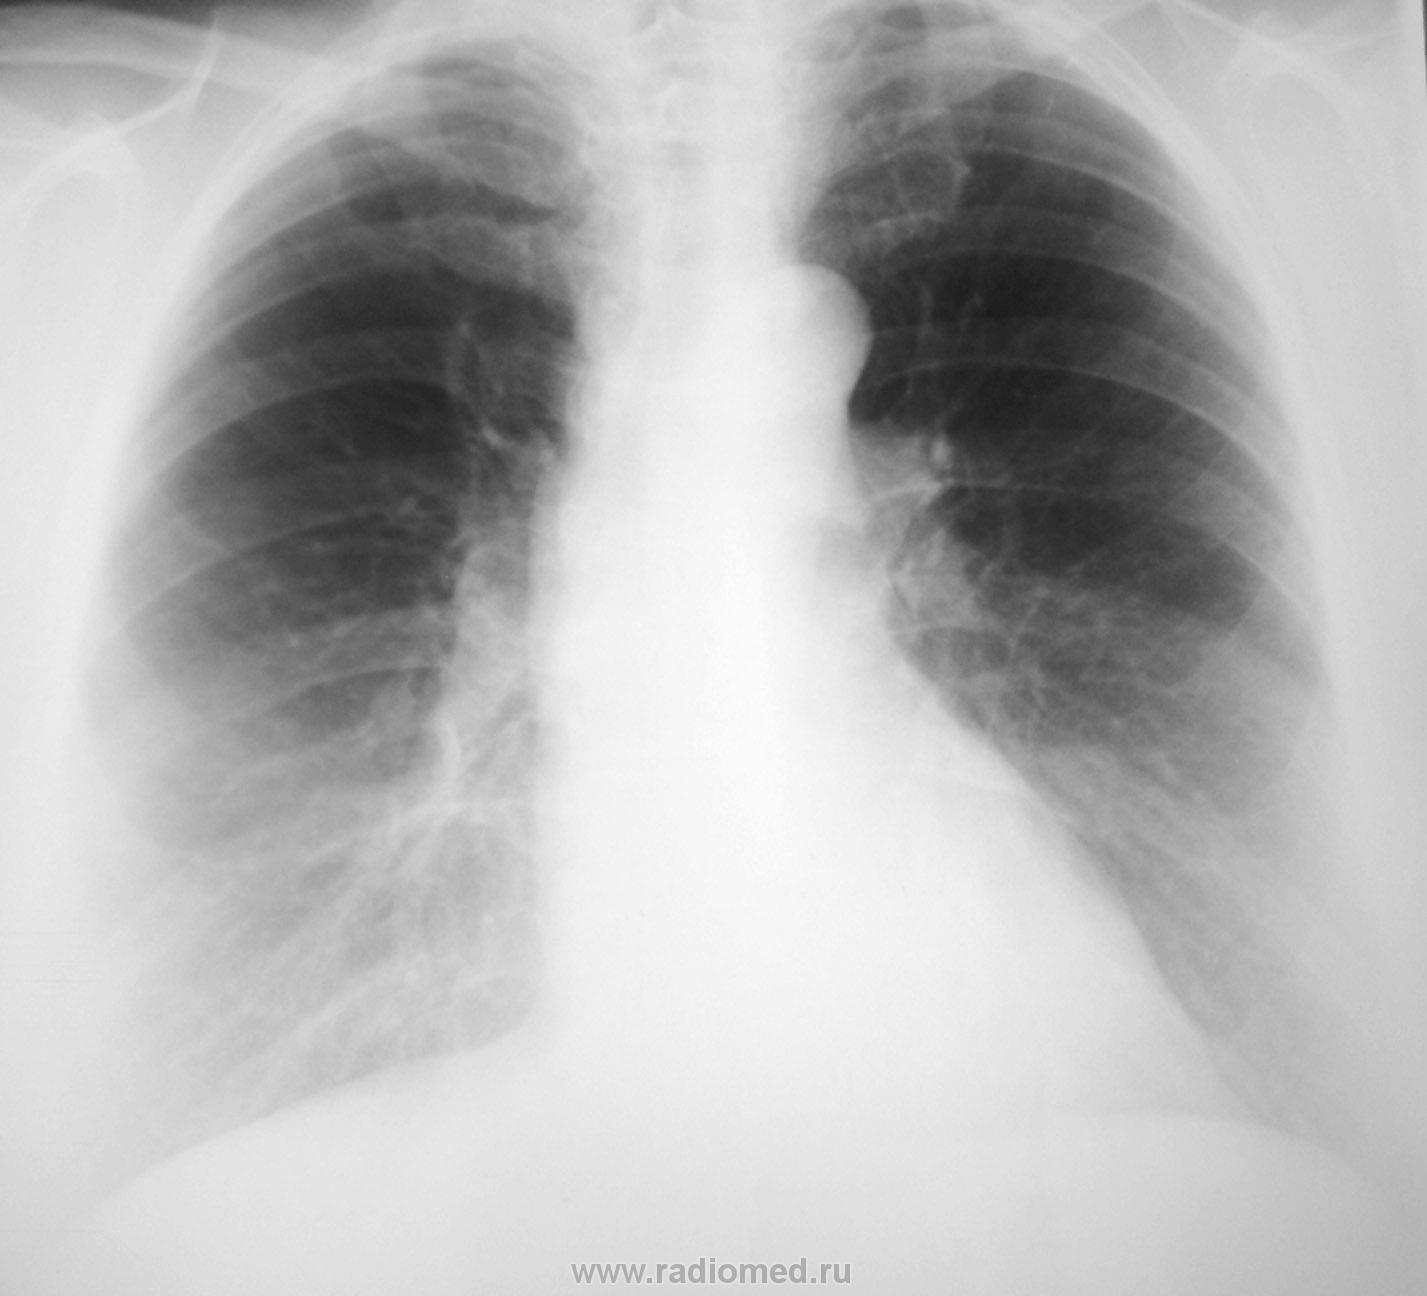

Женщина среднего возраста. Решила "провериться". Беспокоят периодические боли в левой ½ грудной клетки, иногда одышка.

Нет ли очаговой тени в S3?

Только версия!)) Периферический слева. Справа - не уверена, но тоже шарик. Линейные томограммы и предыдущие ФЛГ пожалуйтеsmiley

Слева в переднем синусе - плевродиафрагмальная шварта

Смущает рисующаяся округлая тень на фоне переднего отрезка IV ребра справа

Ничего особенного не заметил. Если бы такой экземпляр на флюорографии - поставил бы норму не задумываясь. Хотя, пытаясь поиграть с изображением насмотрел что-то плевральное в переднем синусе.

Получается, с моим первым впечатлением ничьё мнение не совпало... А насторожило меня вот ЭТО:

Стало ясно: патологический очаг d = 1см средней интенсивности, четко очерченный, неправильно-округлый находится справа, чуть ниже IV ребра, вблизи передней костальной плевры. Что и подтверждается прицельной рентгенограммой в оптимальной проекции.

ИТАК: Имеем патологический очаг d = 1см, средней интенсивности, с четким, но не очень ровным контуром, неправильно-округлый, находится справа, на уровне нижнего края IV ребра, вблизи передней костальной плевры (по-видимому в S3).

Остается решить: что ЭТО такое? И как с ним поступить?

Мнения Учёных и Практиков какие будут?

Слева суммация теней, а мое воображение нарисовало несуществующую теньsad... Про родинку написала, не подумав о величине бюста пациентки. Так что родинка отпадает. Остается вопрос: где предыдущие ФЛГ, какого размера там была эта штука и была ли вообще... Есть ФЛГ от 2010, декабрь - тут тень эта есть, но тогда за почти 5 месяцев размер тенюшки не увеличился, ИМХО)). Нужны более старые флюшки. И если картина не меняется - "добро". На КТ направлять однозначно, даже если не увеличилась. С диагнозом субплеврального образования S3 справа, и "добро" нуждается в дообследовании (спасибо Ola-la и Петровичу за придание ускорения и верного (?) курса)laugh

Но, хотя ОНО в динамике ведёт себя вполне доброкачественно, направлено в ПТД, для исключения туберкуломы.